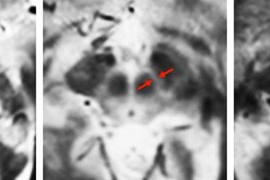

This approach could also be applicable to Parkinson’s disease, a degenerative neurological disorder that kills dopamine-producing cells in the brain’s substantia nigra, leading to tremors, slowness of movement, and difficulty walking.

Preliminary results from a study of 21 Parkinson’s patients and 15 healthy subjects suggest that there is greater variation in the keystrokes of Parkinson’s patients than in control subjects, Sanchez-Ferro says. If the findings are validated in larger studies, the researchers believe this approach could lead to earlier diagnosis for Parkinson’s and aid in the development of better treatments. Currently, there is no way to diagnose Parkinson’s in early stages of the disease.